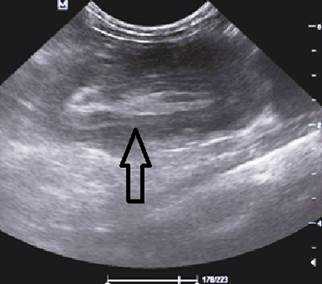

Комментарии: основным методом в дополнительной диагностике инвагинации кишечника является УЗИ органов брюшной полости. Этот метод обладает 100-процентной диагностической достоверностью и специфичностью в отношении инвагинации кишечника. УЗ-признаками инвагинации кишечника является обнаружение симптома «мишени» или «псевдопочки». Симптом «мишени» заключается в наличии на поперечном срезе двух колец низкой эхоплотности, разделенных гиперэхогенным кольцом. Симптом «псевдопочки» виден на продольном срезе и представляет собой наслаивающиеся друг на друга гипер- и гипоэхогенные слои.

Золотым стандартом считается проведение ультразвукового исследования (сонографии) органов брюшной полости, так как оно является неинвазивным, быстрым, безопасным, безболезненным и высоко информативным методом. [9] [10] При помощи сонографии можно диагностировать инвагинат не только на типичных, но и на атипичных участках кишечника, что повышает точность установления и верификации диагноза.

В момент УЗ-исследования врач может определить один из симптомов:

- симптом мишени (за счёт внедрения одной кишки в другую инвагинат на срезе выглядит как мишень);

- симптом "почки с завоздушенным центром".